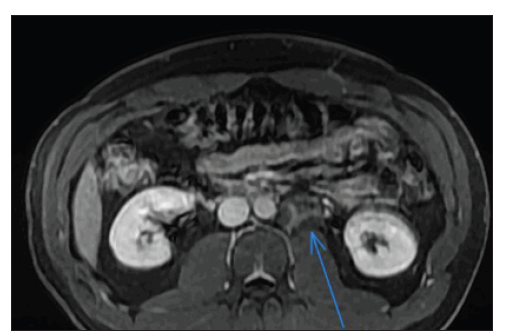

Figure 1:MRI.

A 32-year-old male patient without comorbidities presented with sporadic abdominal pain. He had not undergone abdominal ultrasound due to SARS-COV-2 pandemic. In November he felt symptoms compatible with COVID-19, latter on confirmed with a PCR test. Patient underwent chest tomography and was found incidentally a retroperitoneal mass, left paraaortic, at the level of the renal hilum on this side, with approximately 3.4cm, appearing to contain internal fatty areas, partially included here. It was necessary to proceed with diagnostic investigation, preferably through MRI of the upper abdomen for further elucidation. In view of the findings, he performed an abdominal MRI scan (Figure 1) that identified: expansive heterogeneous and lobulated retroperitoneum para-aortic lesion on the left, just below the renal vessels on this side, measuring 5x5x3.5x3.2cm. It presented heterogeneous hypersignal in T2-weighted sequences, discreet and late enhancement and spots of micro and macroscopic fatty content. There was little insinuation of the lesion in the left anterior pre-vertebral space (level L1 / L2), without compromising the intervertebral foramen or adjacent organs. The possibility of injury to the mesenchymal lineage (mainly a liposarcoma) should be considered, admitting differential with injury of neural or paraganglionic origin. Computed tomography-guided lesion biopsy of the lesion suggested neuroblastic neoplasia with ganglioneuroma characteristics [1,2]. Due to the findings, the patient underwent retroperitoneal tumor resection and robotic retroperitoneal lymphadenectomy with the Da Vinci XI robot. Patient was positioned in a left flank position and five ports were introduced transperitoneally. Intraoperative ultrasound was performed for the precise identification of the lesion and cautious tumor dissection and resection was performed, which had minimal contact with the left renal vein (Figure 2). The procedure took about 150 minutes, with an estimated loss of 80mL of blood and the patient was discharged on the 3rd postoperative day. The anatomopathological examination revealed a maturing ganglioneuroma a peripheral neural sheath neoplasm consisting mainly of a schwannomatous component and mature and in-between maturation ganglion cells. Classification INPC (International Neuroblastoma Pathology Classification) - favorable histology [3,4].